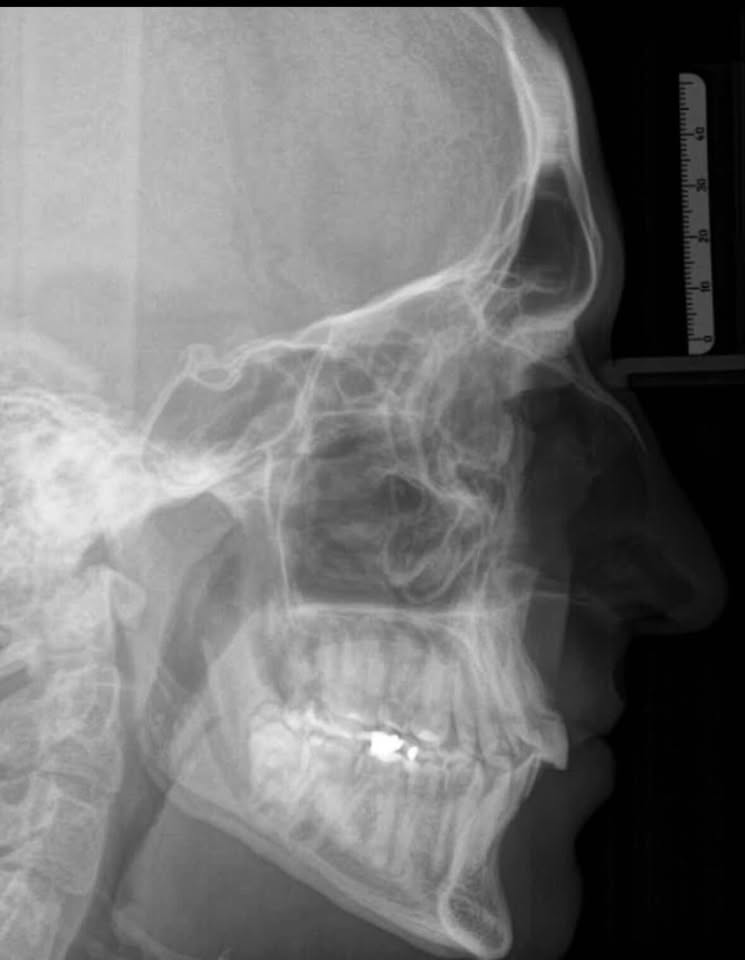

Is lefort1 gonna help me fix my negative orbital vector alone, or do i need to go for implants/fat grafting after djs.